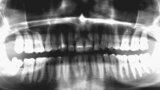

Fig. 4: Initial situation, panoramic radiograph (2015).